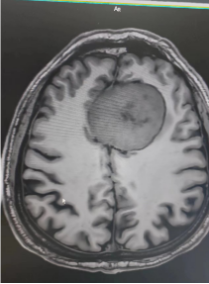

开展“脑健康”筛查

脑血管病和认知障碍是影响脑健康的重大神经系统疾病,位居前两位。随着人口老龄化的趋势,上述疾病给个人、家庭和社会带来了沉重的经济和社会负担。本着早筛查早预防的原则,准确的风险评估,是科学预防的始动环节。

为积极有效地落实院领导集体对离退休职工关心和关爱,健康管理中心、离退休职工办公室、国家神经系统疾病影像中心和神经心理科,在5月份开始共同开展“脑健康”专项体检工作。并采取适宜的干预措施,预防认知功能减退的进一步发展,将有利于医院退休职工人群的生活质量提升。

“脑健康”专项体检包括头部磁共振(MRI+MRA,部分包括 fMRI)、认知功能评价(MoCA)等评估项目。促进脑重大疾病风险的准确评估,并给与针对性的建议,科学预防脑重大疾病,有效促进脑健康水平。